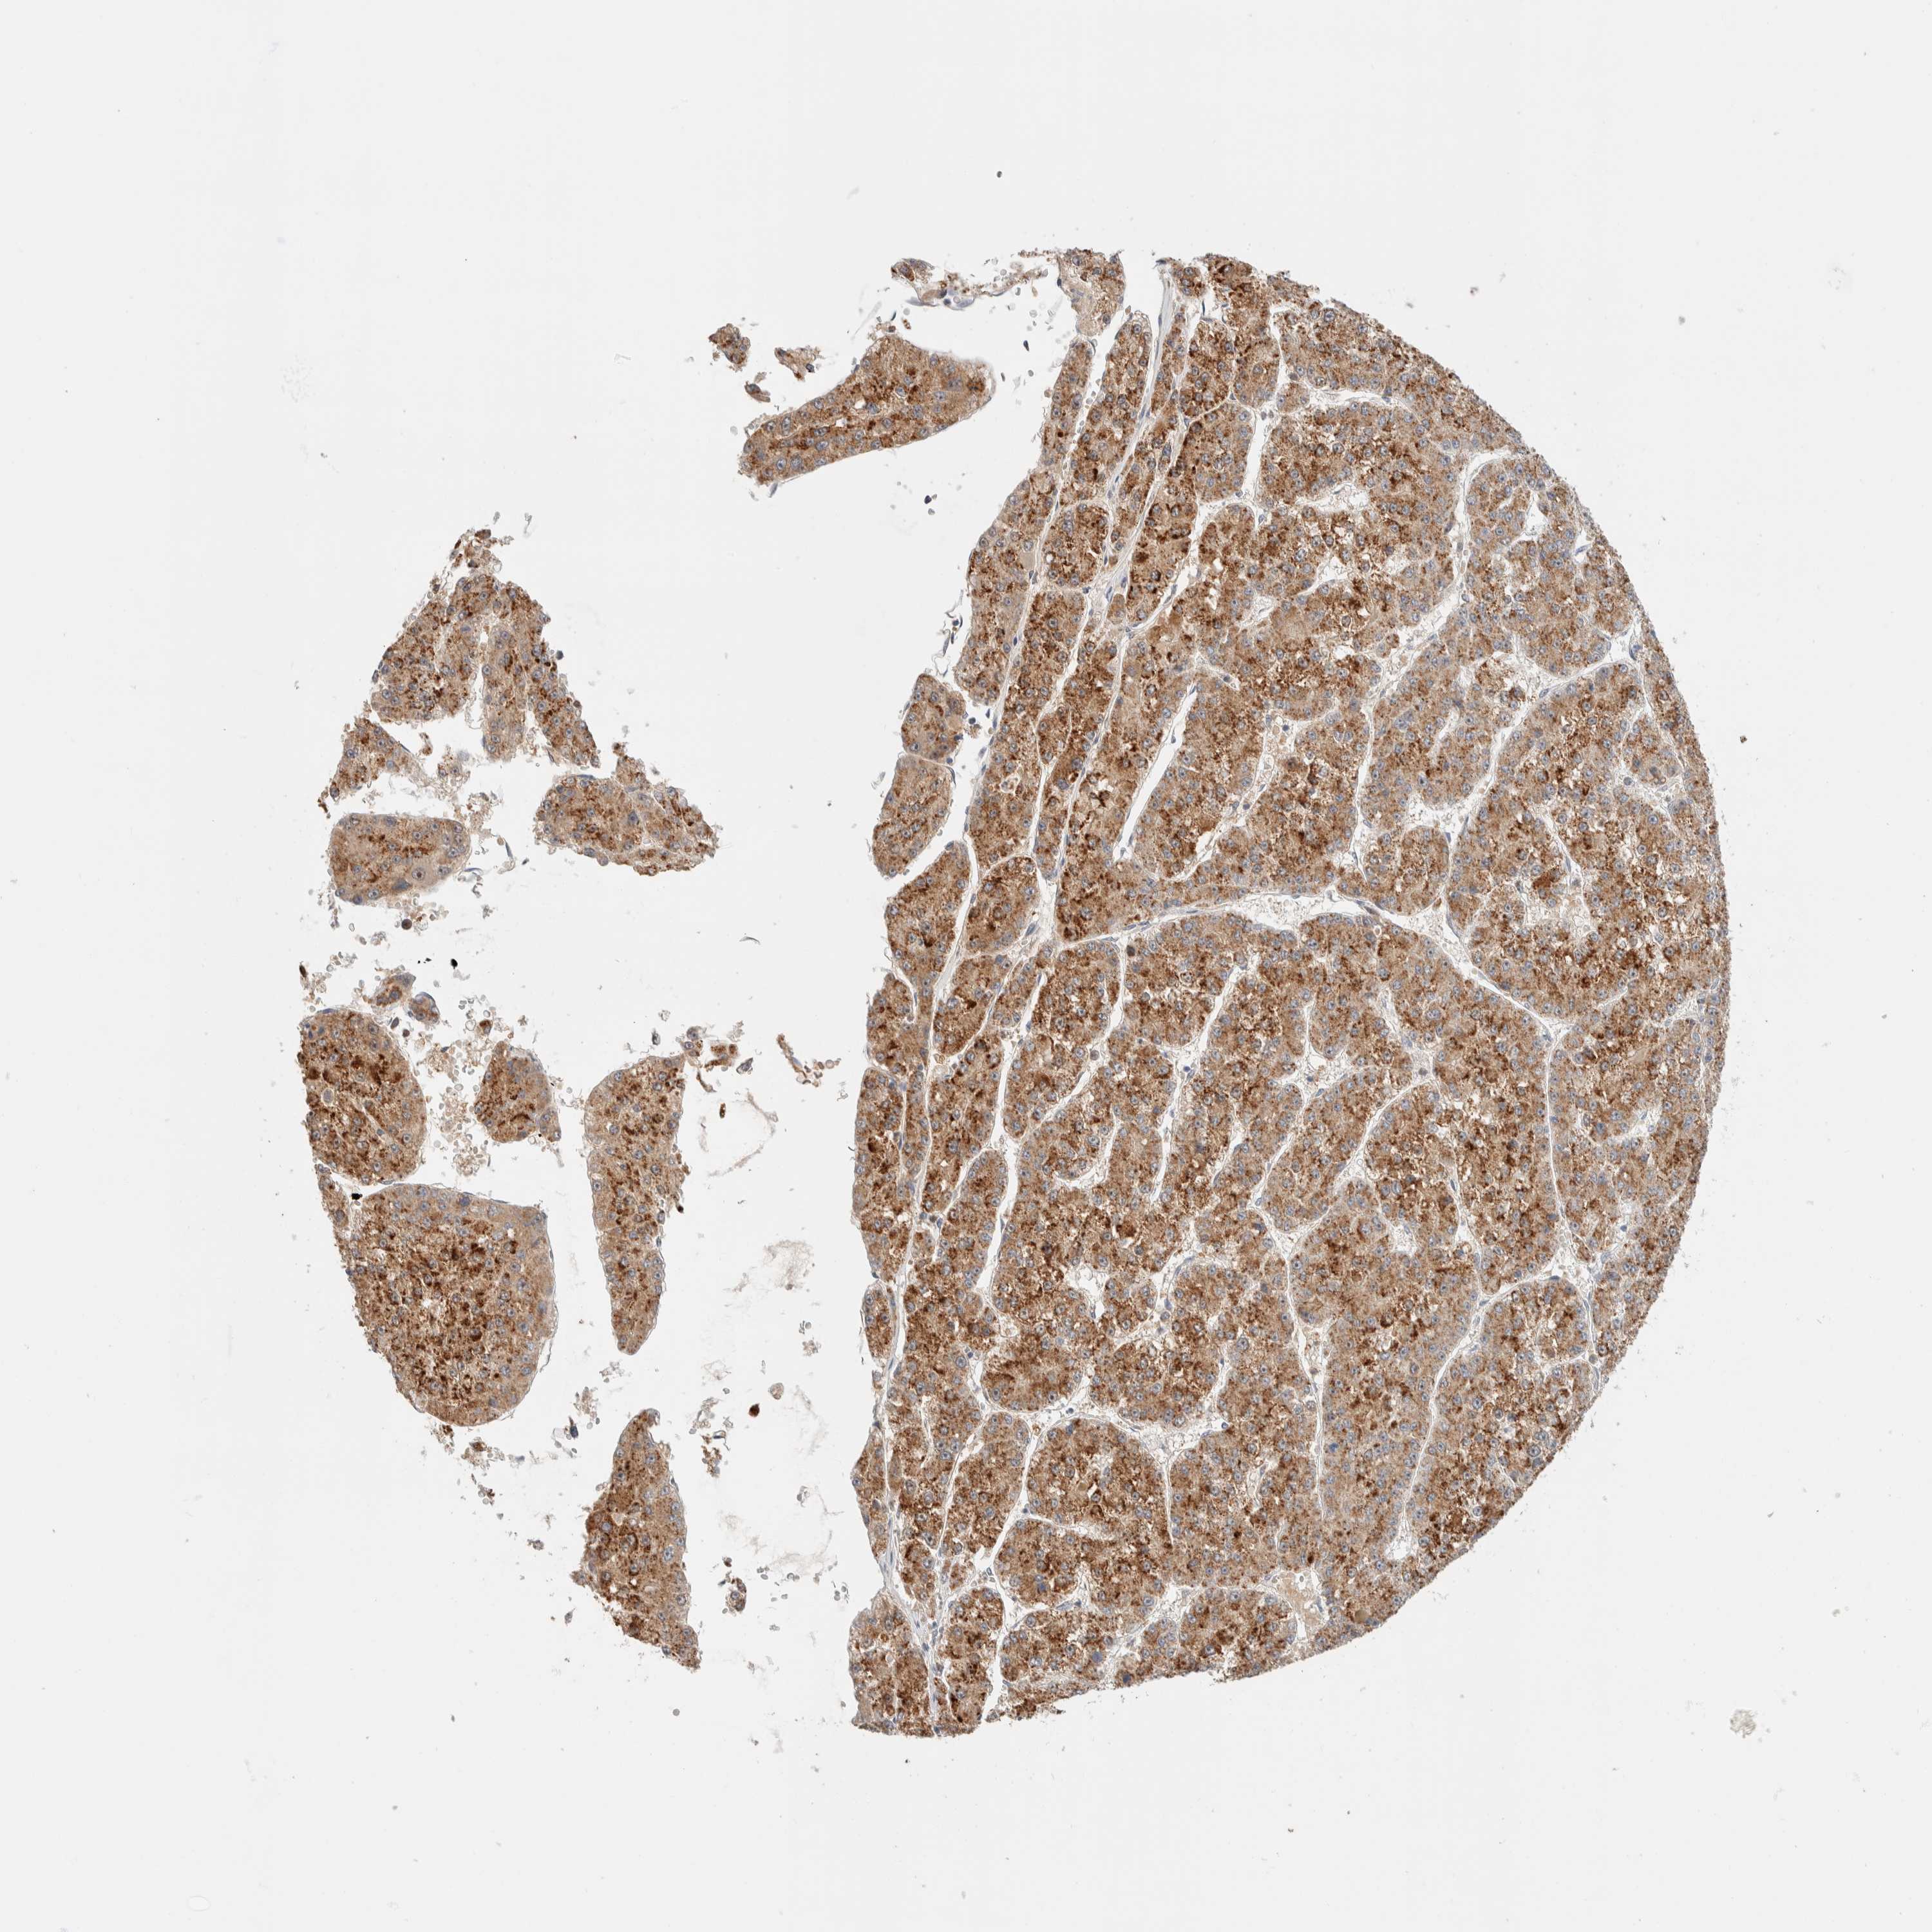

LIVER CANCER - Protein expressioni

A mouse-over function shows sample information and annotation data. Click on an image to view it in a full screen mode. Samples can be filtered based on level of antibody staining by selecting one or several of the following categories: high, medium, low and not detected. The assay and annotation is described here.

Note that samples used for immunohistochemistry by the Human Protein Atlas do not correspond to samples in the TCGA dataset.

Antibody stainingi

Antibody staining in the annotated cell types in the current human tissue is reported as not detected, low, medium, or high, based on conventional immunohistochemistry profiling in selected tissues. This score is based on the combination of the staining intensity and fraction of stained cells.

Each image is clickable and will lead to virtual microscopy that enables deeper exploration of all samples and also displays staining intensity scores, fraction scores and subcellular localization as well as patient and tissue information for each sample.

Antibody HPA020427

Antibody HPA024158

Antibody HPA024585

Staining

High

Medium

Low

Not detected

Intensity

Strong

Moderate

Weak

Negative

Quantity

>75%

75%-25%

<25%

None

Location

Nuclear

Cytoplasmic/membranous

Cytoplasmic/membranous,nuclear

Cholangiocarcinoma

Carcinoma, Hepatocellular, NOS